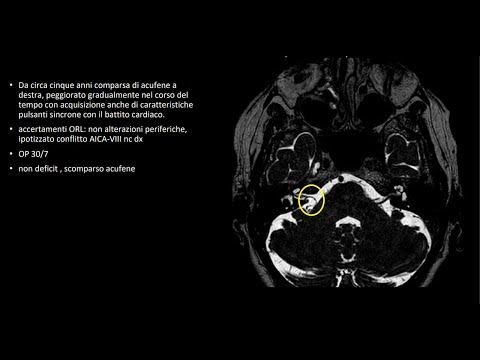

Hellow guys, Welcome to my website, and you are watching Acoustic neuroma. and this vIdeo is uploaded by Antonio Romano Neurochirurgia MO-RE at 2018-01-22T13:38:48-08:00. We are pramote this video only for entertainment and educational perpose only. So, I hop you like our website.